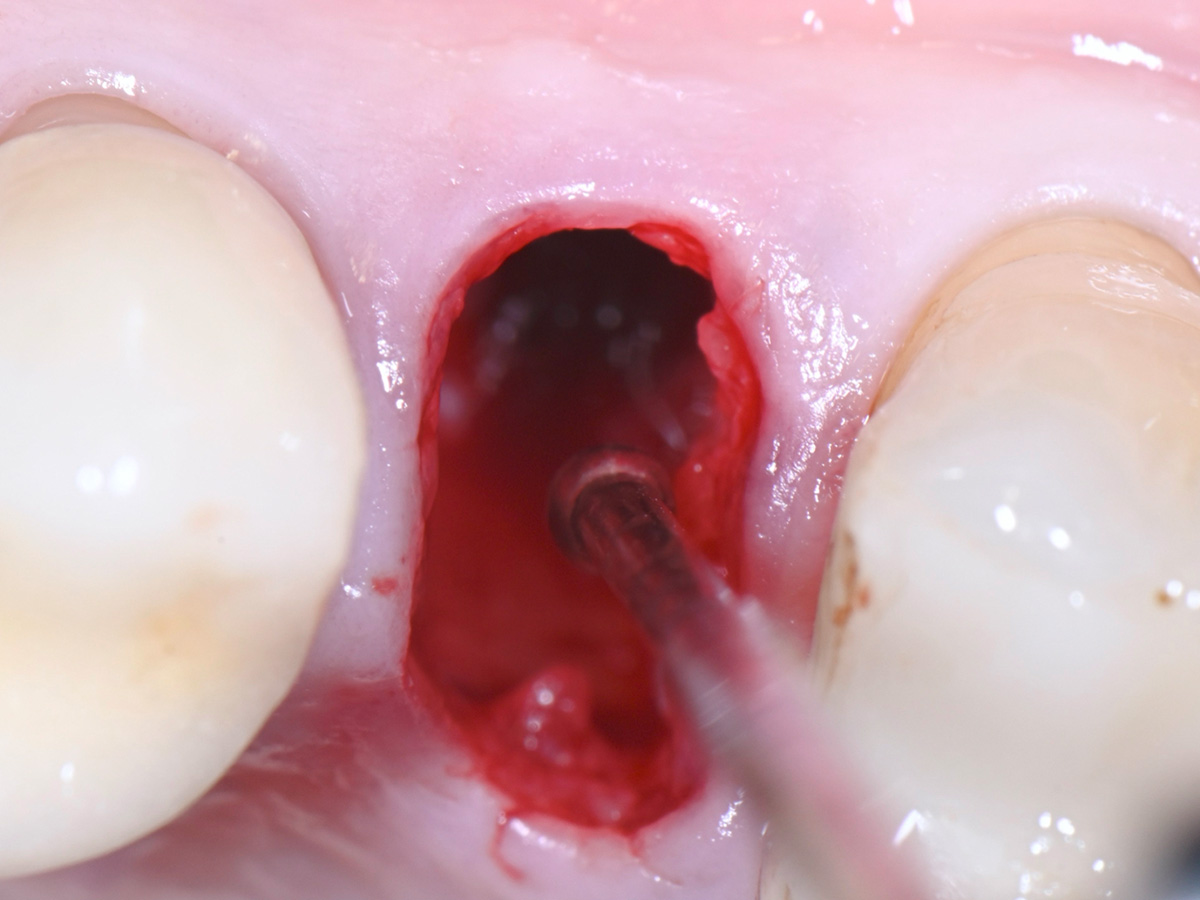

Abbildung 6

Entfernung des entzündlichen Gewebes aus der Extraktionsalveole

Abbildung 7

Sondierung der Extraktionsalveole mit einer Kugelsonde